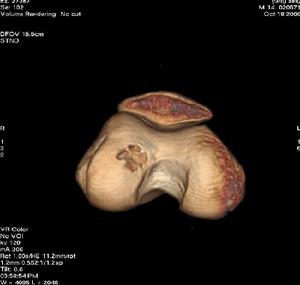

已往曾被命名為“成骨性纖維瘤”、“巨型骨樣骨瘤”等,病理性骨折

目前均已被廢棄。本病很少見。腫瘤的主要組織成分為血管豐富的骨樣組織,新生骨質以及大量骨母細胞。隨著腫瘤發展上述組織可相繼引起各種變化,因此難與骨巨細胞瘤及骨肉瘤鑑別。過去本病一直被認為屬良性腫瘤,近年有肺部轉移病例的報導,但其組織學檢查在此時仍無明顯惡變,面其生物行為可能發生惡變故認為有潛在惡性變可能。發病年齡多數在10~25歲之間,女多於男,發生部位以脊柱最多見,手足部次之,其他部位偶爾發生。起病緩慢。大多數患者僅感輕度疼痛。發生在脊柱者可有不同程度的脊髓或神經根壓迫症狀。X線表現可因腫瘤的鈣化或骨化程度而呈各種透明陰影,甚至密度增深陰影。一般腫瘤與周圍骨組織分界清晰,兩者之間常有明顯骨質硬化。在骨皮質時皮質常變薄並有一層骨膜新生骨。治療以手術抓刮植骨為主,病變在脊柱手術不能徹底可在減壓後加用放射治療。骨肉瘤